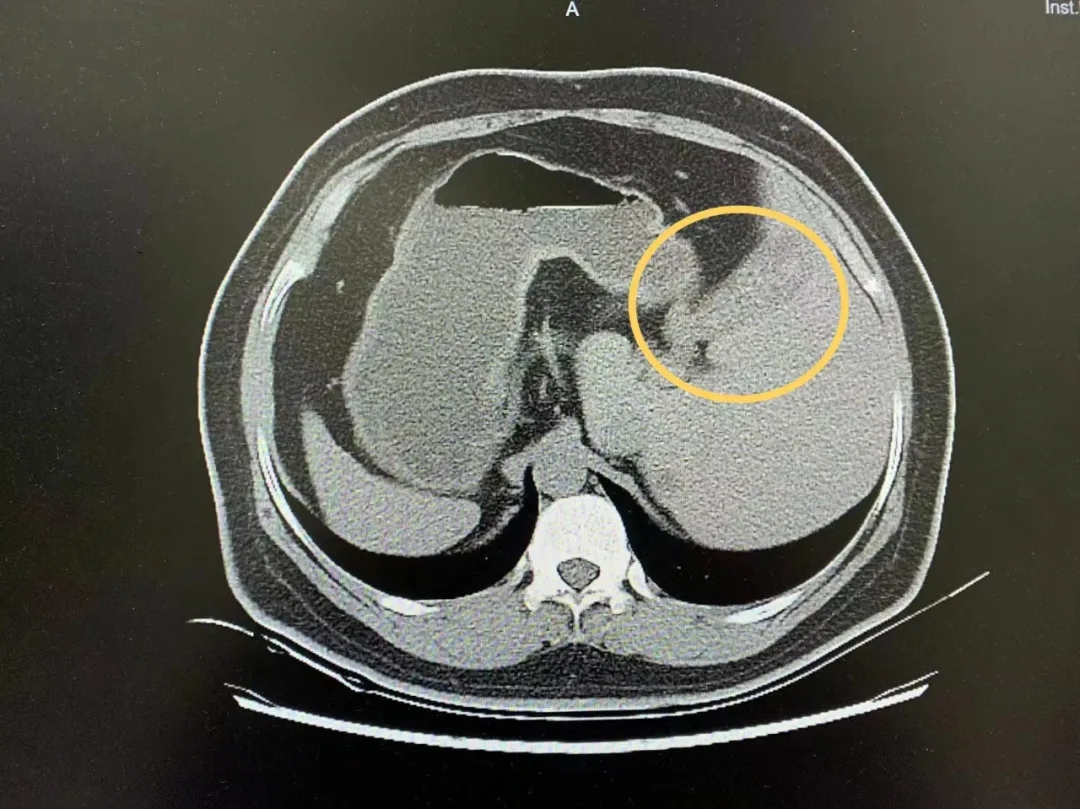

患者胆囊竟位于腹部左侧!

不仅如此,

其他内脏器官位置均镜面翻转,

这就是罕见的“镜面人”。